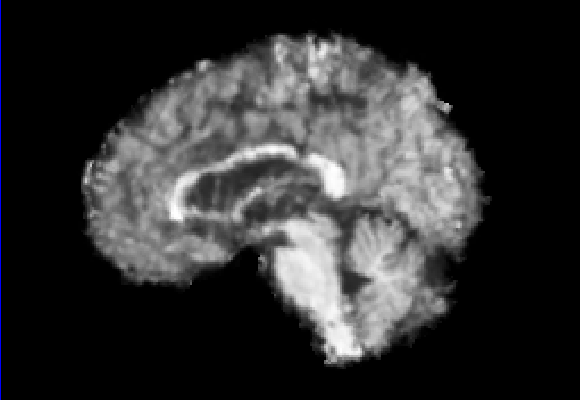

Exp. 1: Segmented adult brain data is used to evaluate our network’s regression performance with known ground truth Tisubscript𝑇𝑖T_{i}. 85 brains from the ADNI data set[1] were randomly selected; 70 brains for ΩtrainsubscriptΩ𝑡𝑟𝑎𝑖𝑛\Omega_{train} and 15 brains for ΩvalidationsubscriptΩ𝑣𝑎𝑙𝑖𝑑𝑎𝑡𝑖𝑜𝑛\Omega_{validation}. Fig. 2 shows an example slice of the ground truth and the reconstructed ΩΩ\Omega.

Figure 2: Example slice from the segmented adult brain MRI data set (a); reconstruction from 300 ωisubscript𝜔𝑖\omega_{i} based on SVRNet regression without SVR (b); SVR initialised with SVRNet predictions after eight iterations of SVR (c). Note that SVRNet (b) predicts individual slice transformations only from image intensities without any initial world co-ordinates of the sampled slice. (d) shows the achieved PSNR in dB when comparing the volumes of (b) and (c) to (a).

Reconstructing from Ti^^subscript𝑇𝑖\hat{T_{i}} initialisation without SVR yields a PSNR of 23.7 ±plus-or-minus\pm 1.09; with subsequent SVR the PSNR increases to 29.5±plus-or-minus\pm2.43 when tested on 15 randomly selected test volumes after four iterations of SVR.